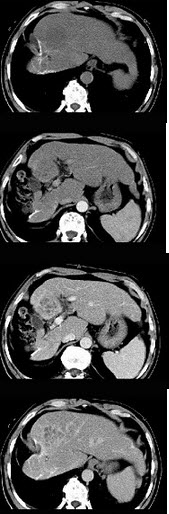

女性,56岁,腹胀、双下肢水肿、乏力、食欲不振,影像所见如下图,最佳的诊断是( )

A:酒精性肝硬化并肝血管瘤

B:血吸虫肝硬化并肝癌

C:肝炎后肝硬化并肝癌

D:局限性脂肪肝

E:原发性肝癌